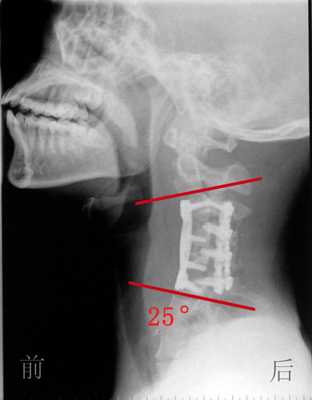

综合国内外文献资料,目前还没有发现颈椎后凸畸形如此严重的病例,且文献资料中所介绍的一次手术矫正畸形的方法大多手术难度大,矫形效果差,手术中脊髓损伤的风险极高。治疗小组决定采用循序渐进的策略,采用松解、牵引复位、最后矫形固定的方法。7月31日,首先为小包做了一个颈椎前后路联合的充分松解手术,该手术创新性地采用了一种全新的“平衡悬吊式牵引”方法,在牵引过程中,将项背部悬空,依靠头颅自身的重量,使颈椎后凸的角度逐渐缩小,通过近4周的“平衡悬吊式牵引”,病人原本125度的颈椎后凸角度已经减少到25度左右。一个半月后,治疗小组又对其进行了一次颈椎前后路的联合手术,这一次,用钛板螺钉内固定的手术方法,从前后方向将颈椎固定。